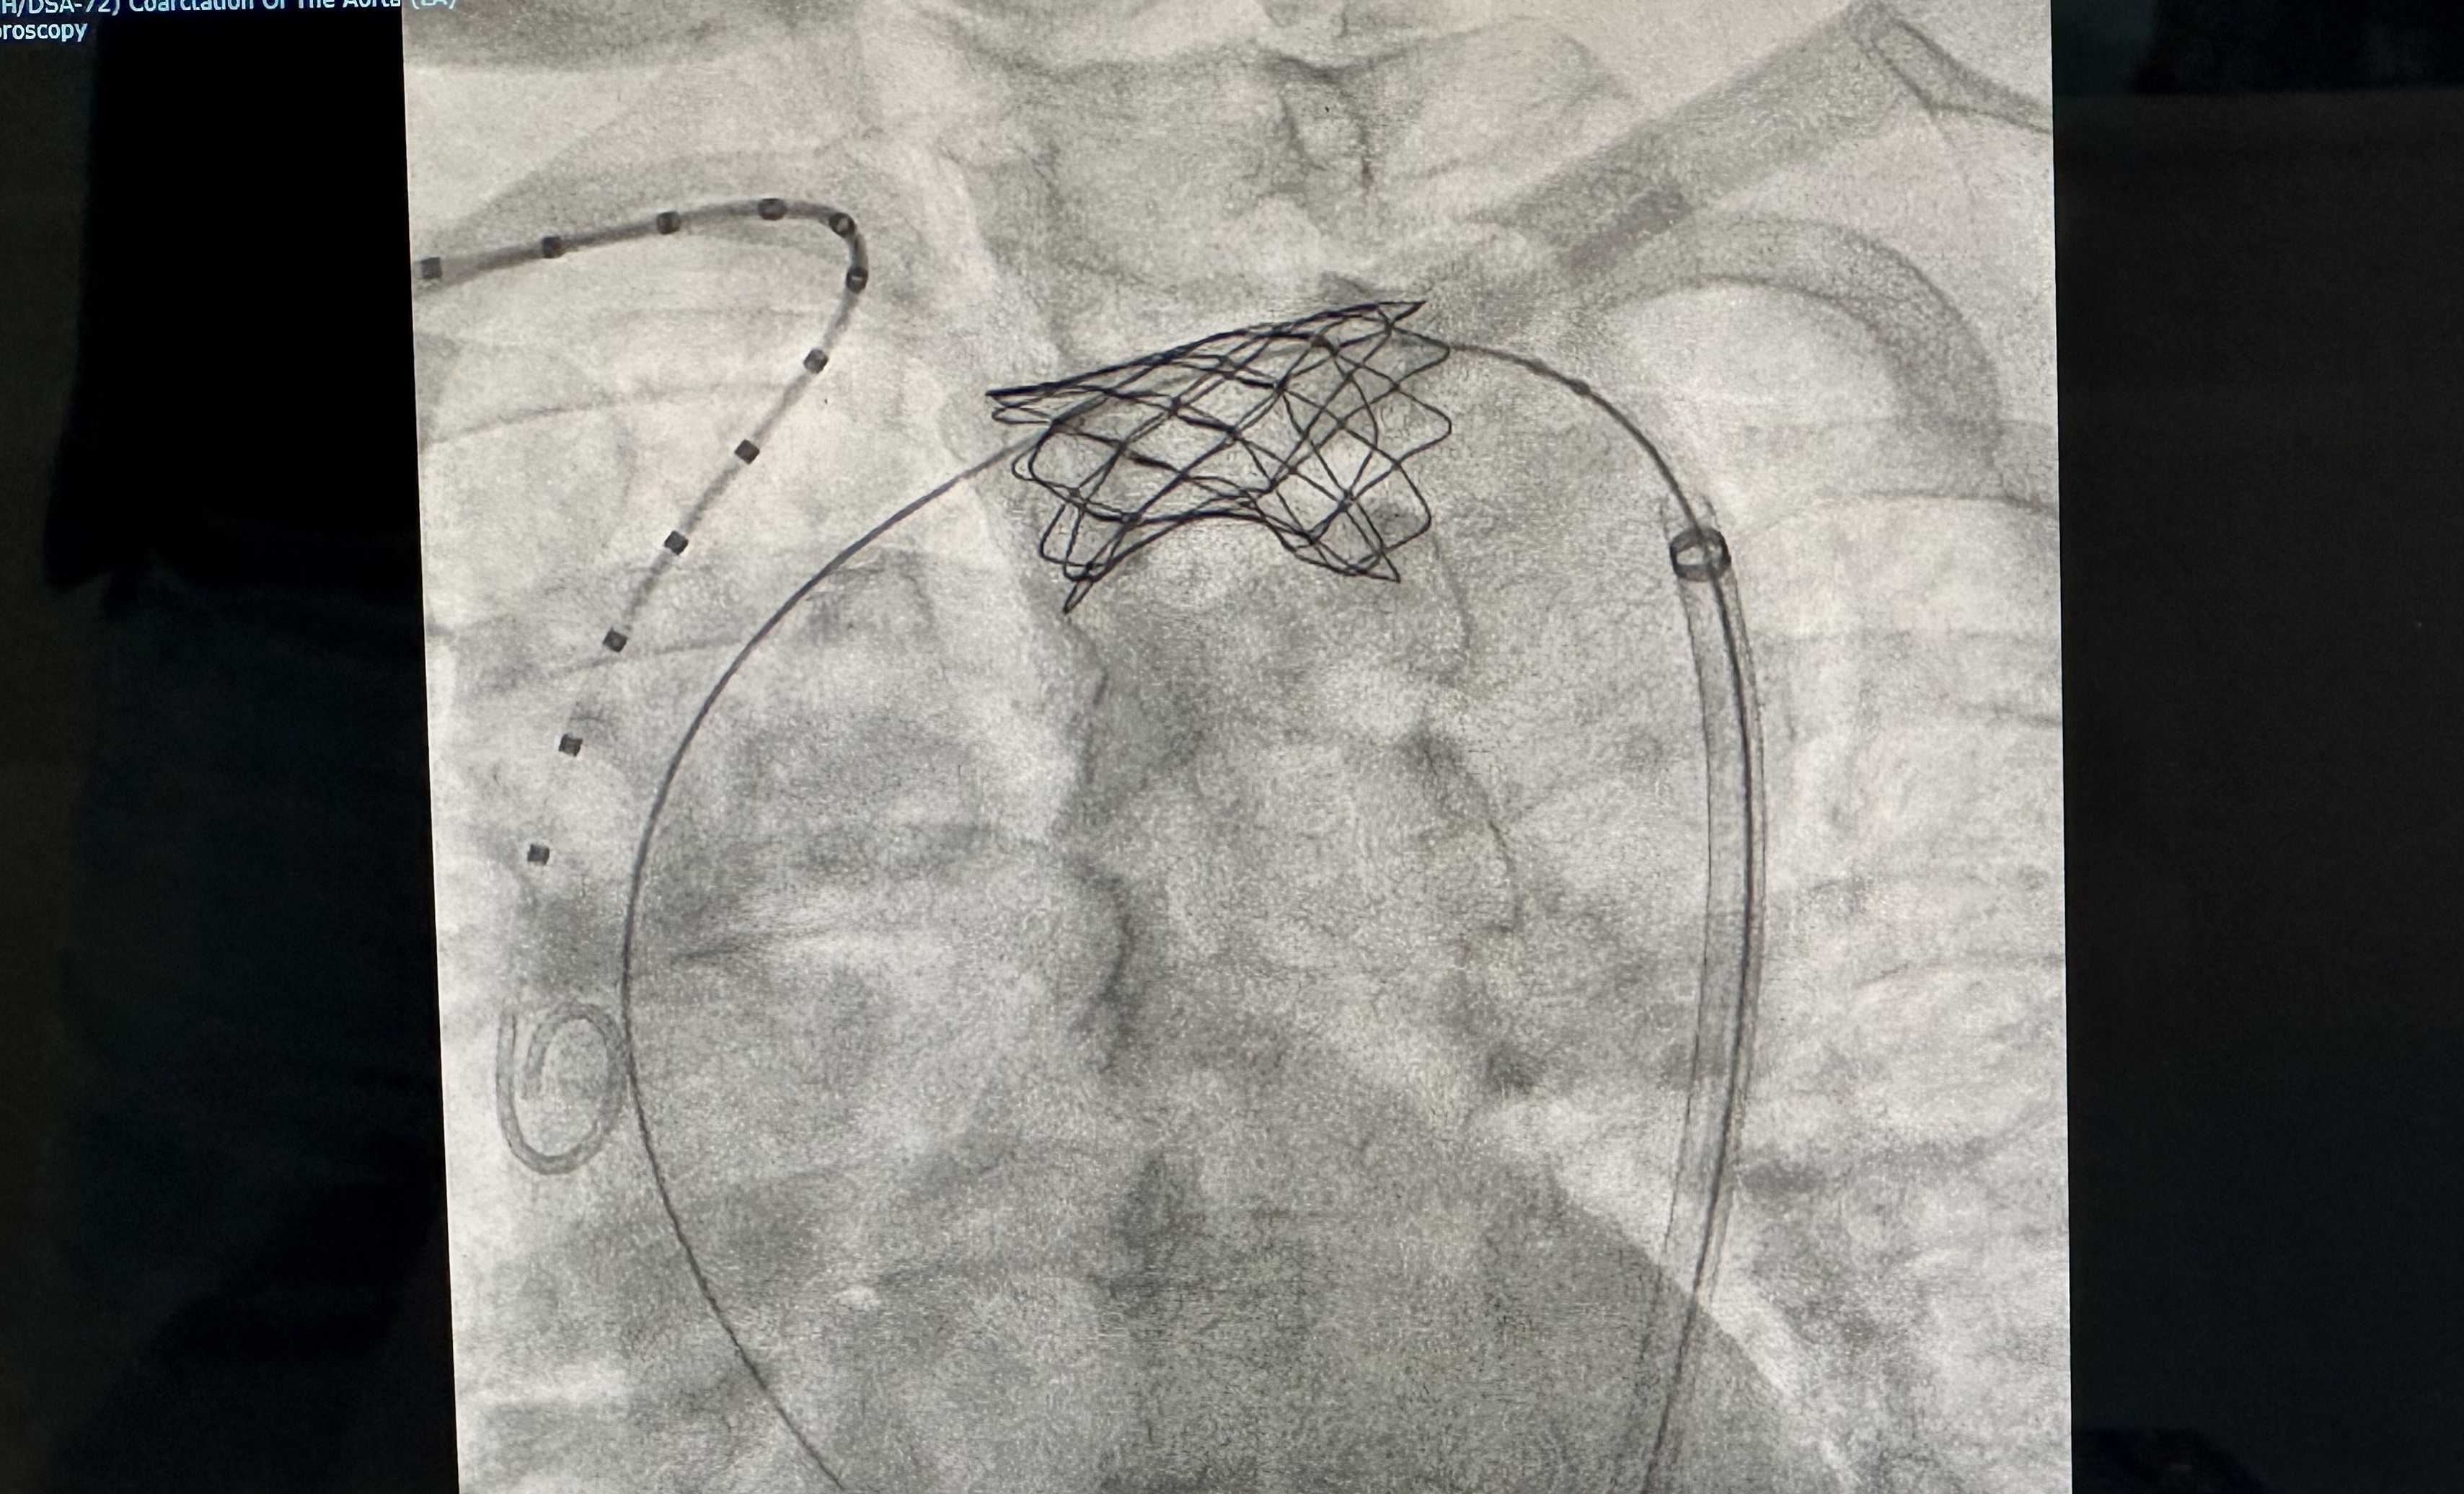

Ngày 26/11, TS.BS Hồ Minh Tuấn trực tiếp thực hiện thủ thuật nong bóng, đặt stent với sự hỗ trợ của máy chụp mạch số hóa xóa nền DSA. Thủ thuật diễn ra thành công sau 60 phút, bệnh nhân trong trạng thái tỉnh táo.

| Hình ảnh stent động mạch chủ được chụp lại sau khi đặt thành công. |